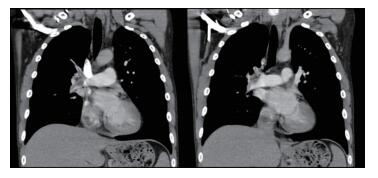

The patient's blood pressure was improved rapidly: 1 hour later, the heart rate was 124 beats/min, blood pressure 95/65 mmHg, respiratory rate 30 /min and oxygen saturation 95% on supplemental oxygen. And cyanotic disappeared (Figure 1B). A second ECG revealed sinus tachycardia with no ST-T wave abnormalities. The diagnosis of pulmonary embolism was made on pulmonary computed tomographic angiography (PCTA) (Figure 2). Subcutaneous enoxaparin 1 mg/kg continued over the next 12 hours. A second PCTA undertaken 30 hours later showed a substantial reduction in the volume of pulmonary emboli and restoration of right pulmonary blood flow (Figure 3). He made a full recovery and was discharged with a plan for long-term warfarin therapy.

Figure 2 PCTA at 2 hours after Ⅳ enoxaparin showed right trunk and left pulmonary artery embolism. |

Figure 3 PCTA at 32 hours after Ⅳ enoxaparin showed reduction in the volume of pulmonary emboli and restoration of right pulmonary blood flow. |